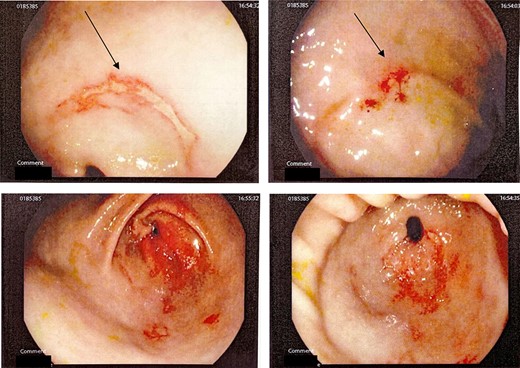

This is a case of a 12-year-old Caucasian female with a background history of autism spectrum disorder presented to the emergency department of a rural hospital in Australia after the ingestion of two NiMH batteries. This is the third presentation of battery ingestion in 2 weeks. She was asymptomatic and did not complain of abdominal pain at the time of review. On examination, she had a soft abdomen with mild epigastric tenderness and guarding. Abdominal radiograph showed the presence of two battery structures projecting to the left of the upper abdominal area overlying L1/2 discs (Fig. 1). To the right of L2, there are two other round devices resembling metallic-type foreign bodies. A gastroscopy was performed 3 hours after her presentation. The gastroscopy revealed extensive superficial erosion to the antral and greater curvature (Fig. 2). Two NiMH batteries were retrieved. However, the other two smaller foreign bodies have passed the jejunum proximally and were unable to be retrieved. She was discharged home on sucralfate, pantoprazole and ColonLYTELY to promote passage of the remaining foreign bodies. Abdominal X-ray was repeated after 1 week, which showed no further foreign objects retained in the patient’s body. She recovered uneventfully with no development of any residual symptoms.

Gastroscopy showing extensive burns in antral and greater curvature of stomach.